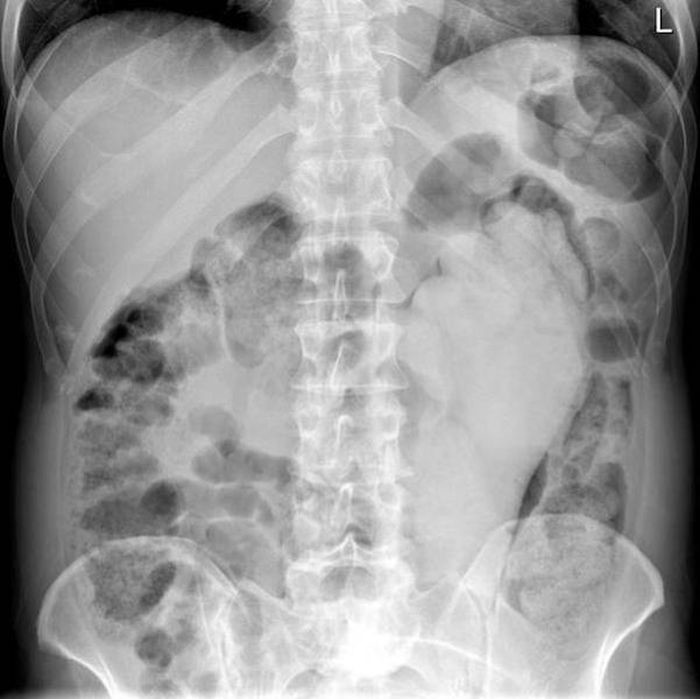

Предметы, которые не очень хочется видеть внутри себя

Под рентгеновскими лучами порой видны не только внутренние органы и кости, но и инородные тела, попавшие в организм

Истории попадания этих предметов в организм могут быть самыми невероятными и запутанными, но больше всего медиков интересует процесс их извлечения, впрочем, в этом заинтересованы и сами пациенты, допустившие нечто подобное со своим телом.